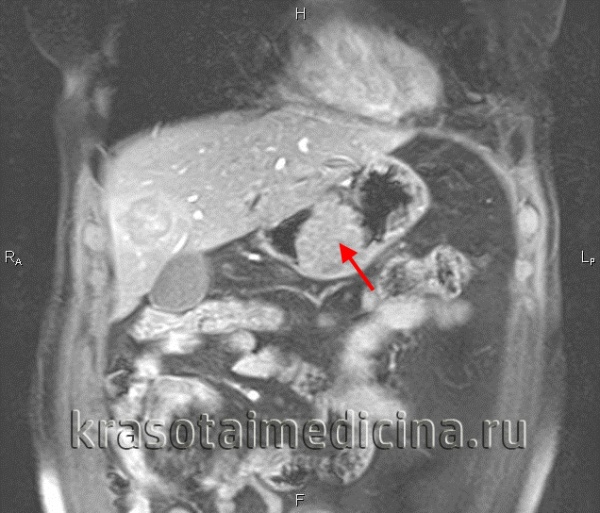

- КТ органов брюшной полости, грудной клетки и головы с внутривенным контрастированием — онкопоиск. Позволяет уточнить, поражены ли лимфоузлы, есть ли метастазы в других органах.